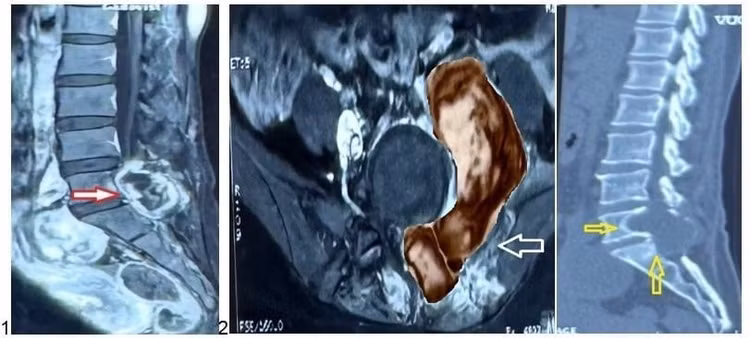

Hình 1, 2, 3: Ảnh chụp MRI và CT Scan trước phẫu thuật của bệnh nhân L. cho thấy khối u kích thước lớn (hình 2, mũi tên đỏ) xâm lấn các cấu trúc lân cận (hình 2, mũi tên trắng) và gây hủy xương vùng cột sống cùng (hình 3, mũi tên vàng) - Ảnh BVCC

Kết quả chụp MRI cột sống thắt lưng cho thấy một khối u lớn dạng “hình quả tạ” ở vùng L5-S1, xâm lấn nhiều vị trí gồm cơ cạnh sống, cơ psoas (cơ thắt lưng chậu), thân sống, cánh chậu và cả vùng phúc mạc. BS.CKII Lê Điền Sơn, Phó trưởng khoa Ngoại Thần kinh – Bệnh viện Nhân dân 115, chia sẻ:

“Khối u nằm đúng vị trí phẫu thuật cũ, có hình ảnh phát triển bất thường. Do đó, chúng tôi nghĩ nhiều đến khả năng u tái phát, thậm chí có thể mang tính chất ác tính”.